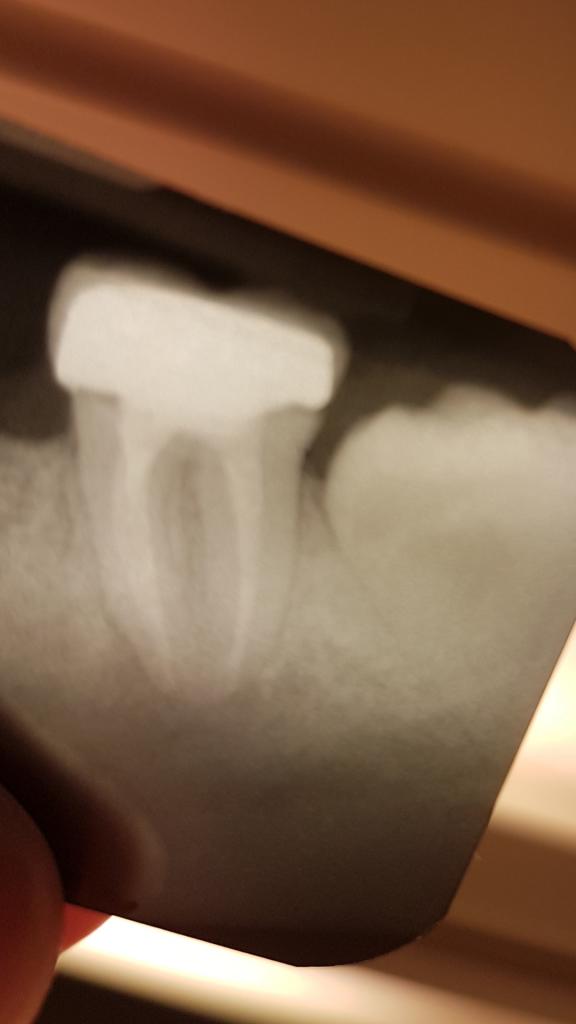

8-ка не лежит в теле челюсти. И просто горизонтально не лежит.Она просто недопрорезалась. Причём она не вся в кости, просто коронковая часть под слизистой. На 7-ку она и близко не давит. Между ними расстояние в миллиметр. И к кисте 7-ки она не имеет никакого отношения.

Можно эту 8-ку и не трогать. Другой вопрос, что если она начнёт когда-то двигаться под влиянием какого-то воздействия - она может упереться в коронку, не важно, на чём эта коронка будет - на перелеченом 7-м зубе, или на импланте, и начнёт сталкивать коронку с опоры. И в этом случае, по-любому, перед перецементировкой коронки Вам этот зуб придётся удалять.

К сожалению, корень 8-ки весь не виден, но даже по тому кусочку, который захвачен снимком - никаких особых проблем с удалением этой 8-ки возникнуть не должно. Канал с нервом сбоку, а не под корнем, корень (корни) - тоже не должны быть особо проблемными. Хотя, если решите удалять - снимок можно будет и ещё раз сделать.